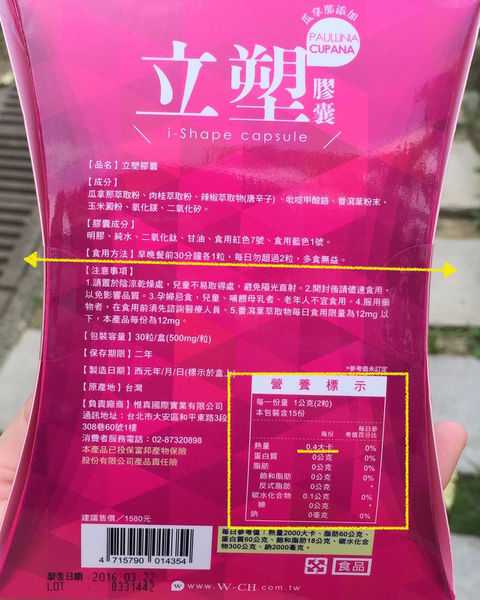

每一盒Supercut塑魔纖立塑膠囊都有三小包,每一小包有10顆膠囊

Supercut塑魔纖立塑膠囊的成分有:瓜拿那萃取粉、肉桂萃取粉、辣椒萃取物(唐辛子)、吡啶甲酸鉻、番瀉葉粉末、玉米澱粉、氧化鎂、二氧化矽。

食用方式:早晚餐前30分鐘各1粒,每日不超過2粒。(多食無益)

番瀉葉萃取物每日食用限量為12mg以下,

番瀉葉萃取物每日食用限量為12mg以下,